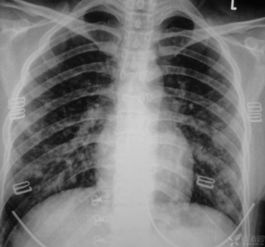

胸片,作为最常用、最基础的影像学检查之一,其核心在于通过X射线穿透人体组织,在胶片或数字探测器上成像。不同密度的组织对X射线的吸收能力不同,从而产生明暗差异,形成影像。理想的胸片影像,应该能够清晰地展现肺部纹理、血管、气管、纵隔结构,以及胸壁、肋骨等骨骼结构。

过曝的隐患:当曝光量过大时,影像会整体偏亮,导致肺部纹理模糊不清,细小的结节、渗出或钙化灶容易被“淹没”在亮白的光晕中,难以辨认。特别是对于早期肺癌等需要精细分辨的病变,过曝的🔥影像无异于“大海捞针”。欠曝的挑战:相反,曝光量不足则会导致影像整体偏暗📝,胸腔内的结构对比度降低,肋骨可能显得过于突出,而肺部实变的区域也可能与周围正常组织界限不清。

这不仅影响了对病灶的观察,还可能导致对一些本应清晰可见的解剖结构的识别困难。“100%”的意义:“100%胸片曝光软件”所追求的,就是一种理想的曝光状态,它能够最大限度地保留影像的细节信息,优化对比度和清晰度,使得医生能够更全面、更准确地观察到🌸每一个微小的变化。